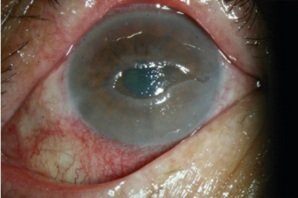

Herpes Zoster

Schwere Kopfschmerzen und Schmerzen in der Stirn treiben einen 74jährigen ins Krankenhaus. Er klagt zudem über ein geschwollenes linkes Augenlid und Lichtempfindlichkeit im selben Auge. Fünf Tage zuvor hat er die zweite Dosis von BNT162b2/Comirnaty in den linken Arm erhalten. Am Tag der Impfung stellt sich eine Empfindlichkeit und Jucken im linken Arm, zwei Tage später in der linken Gesichtshälfte ein, ein Ausschlag auf der Stirn folgt. Der Ausschlag breitet sich schnell über die linke Gesichtshälfte, über Auge und Nase aus.

In der Rückenmarksflüssigkeit des Mannes wird ein erhöhter Anteil weißer Blutkörperchen festgestellt und Varizella Zoster Virus nachgewiesen. Er wird mit Meningitis und Varizella Zoster diagnostiziert.

Augenschaden nach

SCHLANGENGIFTimpfung: Neurothrophes Geschwür

Augenschaden nach SCHLANGENGIFTimpfung: Neurothrophes Geschwür [4]

Nach 10 Tagen wird er entlassen. 20 Tage später ist er wieder da. Diess Mal leidet er an einem neurothrophen Geschwür im linken Auge [siehe Bild] und seine Sehkraft hat sich merklich verschlechtert. Im Verlauf der nächsten zwei Monate verbessert sich der Zustand des Mannes. Seine Sehkraft verbessert sich, kann aber nicht vollständig wiederhergestellt werden. Nach Ansicht der Autoren ist es notwendig, diejenigen, die sich mit COVID-19 Impfstoffen / Gentherapien behandeln lassen, darüber aufzuklären, welche Risiken sich im Hinblick auf eine Varizella-Zoster (VZV) Erkrankung damit verbinden.

“Therefore, we believe that it is important to inform patients about this potential risk and recommend careful monitoring after vaccination given the possibility of VZV reactivation. Early diagnosis and antiviral treatment can halt disease progression and prevent debilitating complications.”

You, In-Cheon, Min Ahn, and Nam-Chun Cho (2022). A Case Report of Herpes Zoster Ophthalmicus and Meningitis After COVID-19 Vaccination. Journal of Korean Medical Science 37(20).